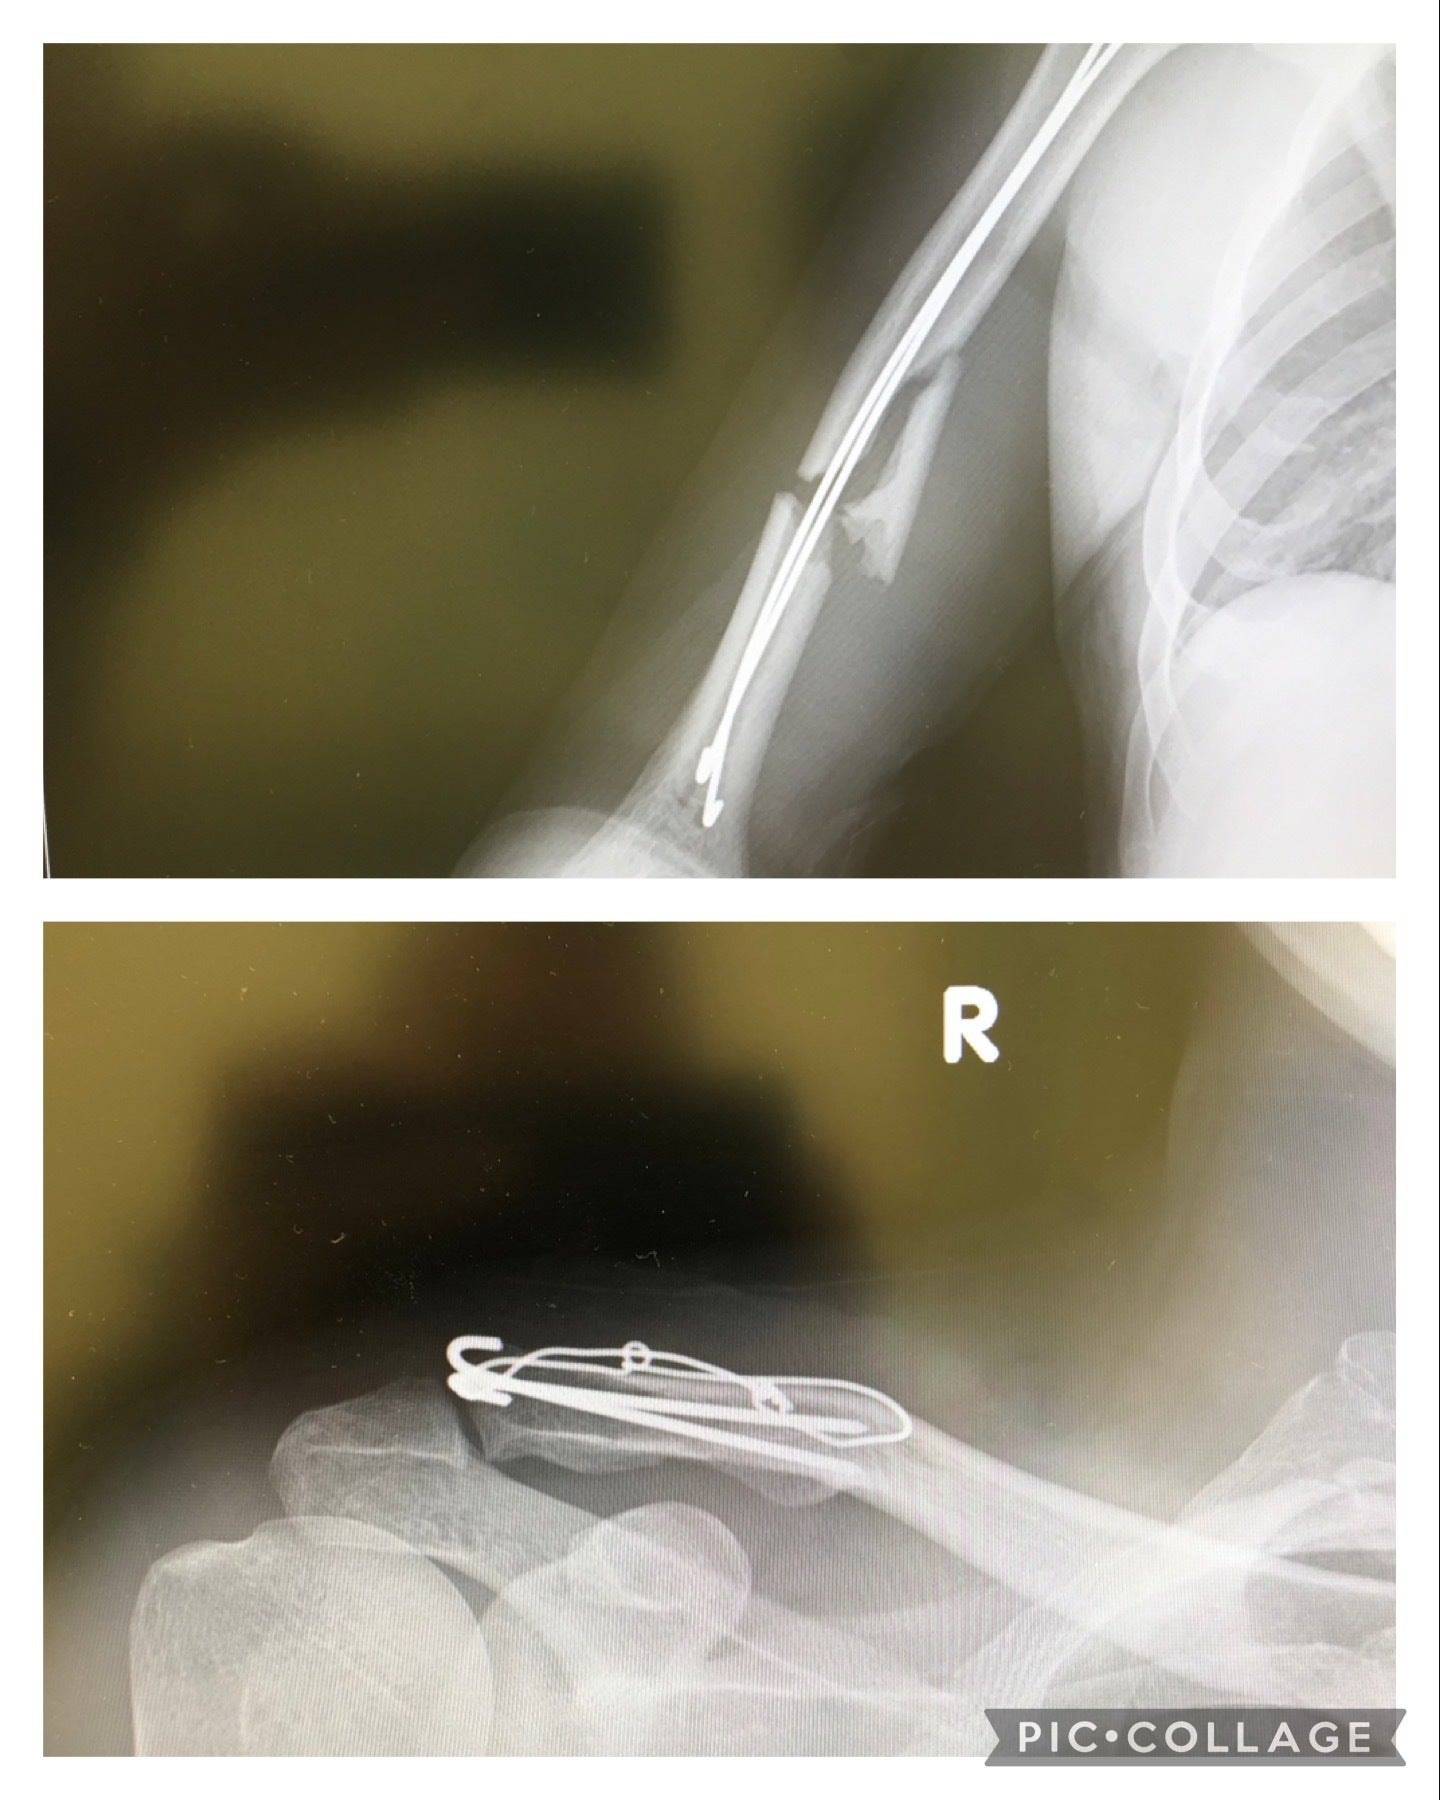

2017年末自身の右腕の骨折、右手の麻痺。

2017鈴鹿NGK杯で転倒右上腕骨折鈴鹿NGK杯のレース中の転倒で右腕を骨折し右手が麻痺。

ドクターから右手は麻痺で動かないと診断されました。アクセル操作やフロントブレーキ操作が出来ないので、

レース人生を諦めようとも考えましたが、

自分なりに考え鍼灸院で、無理やり神経に高電流を流し、激痛に約1時間耐えながら動かすトレーニングを2、3ヶ月しました。

私は、バイクに乗って表現することしか出来ないからこそ、激痛に耐えてでも麻痺を乗り越え戦う意欲しかありませんでした。

約2カ月間トレーニングをして動く様になりましたが、

現在も右手は痺れが残っています。

右手が冷えると、痺れが酷くなり動きが鈍くなります。